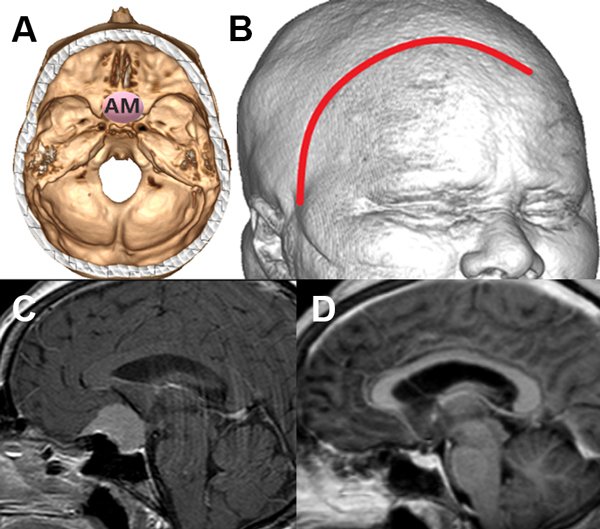

Luego del análisis estadístico propusimos una escala de graduación preoperatoria, con la cual según el puntaje total obtenido podemos inferir la probabilidad de exéresis total. Para la escala utilizamos la localización, el tamaño y la invasión ósea como parámetros (Figura 3, 4 Y 5).

Figura 3: Paciente con meningioma de base de cráneo anteromedial (AM) (1 punto), tamaño menor de 5 cm (1 punto), sin invasión ósea (1 punto), puntaje total: 3, alta probabilidad de resección total. A: localización de lesión en base de cráneo. B: reconstrucción 3D con abordaje. C: resonancia con contraste corte sagital prequirúrgica. D: resonancia con contraste corte sagital posquirúrgica con resección total.